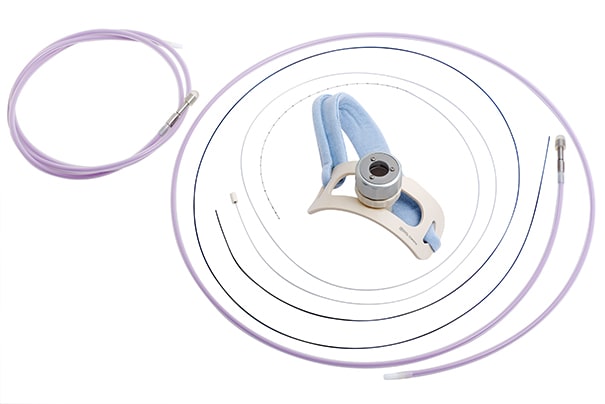

针对肺癌、小细胞肺癌及其他管腔内近距离治疗应用,医科达提供了两种先进的施源器。LumenCare®Azure施源器专门设计用于帮助放疗医师更好地实施肺癌和食道癌近距离治疗,扩大可治疗范围。

LumenCare Azure施源器套件为临床医生提供了肺癌近距离治疗应用的卓越解决方案。该套件专门设计用于更好地实施肺癌治疗,扩大可治疗范围。

LumenCare®施源器——图片由UZL Gasthuisberg(比利时鲁汶)提供